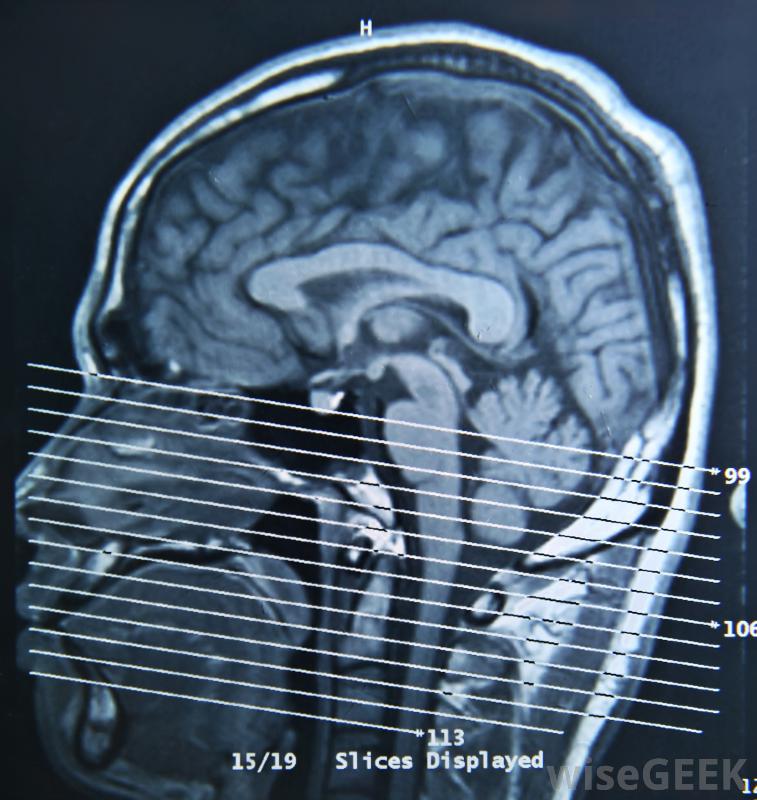

海绵状血管瘤的症状应足以保证使用CT扫描进行进一步调查在大多数情况下,海绵状血管瘤的症状足以支持计算机断层扫描(CT)或磁共振成像(MRI)扫描,这是幸运的,因为这两种类型的扫描通常都能捕捉到其中一种或多种病变的存在决定如何治疗并不是那么简单。

核磁共振成像可以检测出海绵状血管瘤的存在。